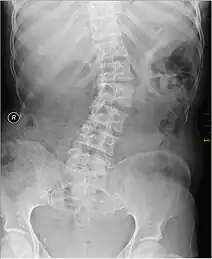

X-ray of individual with scoliosis

Scoliosis has been known to cause unilateral iliocostal friction syndrome.[5] It is a condition in which the lateral curvature of the spine is measured to be more than 10 degrees. Scoliosis is typically categorized into congenital, neuromuscular, idiopathic, degenerative, and pathologic forms.[7] The decreased distance between the ribcage and the iliac crest can come in contact depending on the severity of the scoliosis curve.[8] There has also been reported instances where individuals experience iliocostal friction syndrome due to an abnormally long twelfth rib. This can be presented both bilaterally or unilaterally, depending on the individual.[3][8]